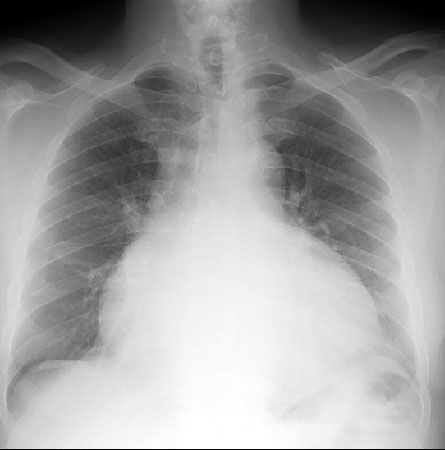

• Рентгенография грудной клетки.

• Эхокардиография: выпот, утолщение перикарда.